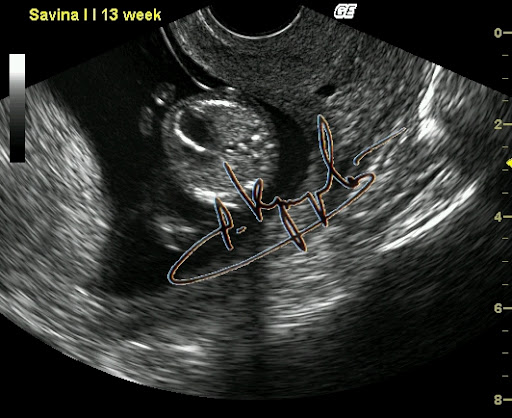

Фиброэластоз эндокарда. Диагностика на ранних сроках возможна.

Вот как быть? Вроде обещал нескольким человечкам рассказать про внутриутробный фак, но совершенно не уверен что получится что-то путнее. Хотя чем черт не шутит. Попробую. Было это буквально на днях, в четверг. Но лучше издалека начать. С именем Настя у меня по жизни непременно связан какой-то налёт чудесатости. Ну есть что-то такое... Что-то буквально на кончике не пойми чего. Как модно говорить "флёр @панутости". То, что даже издалека отличает любую Настю от носительниц других имен. Или, перефразируя вышесказанное, - нормальных Насть я в своей жизни пока не встречал. Это в качестве предисловия, хотя некоторые и осуждают любые эпиграфы. А кто сказал эпиграф? Я сказал - предисловие. Чуете разницу? Нет? Дело ваше. Полумрак кабинета. Беременность 24 недели. И Ваш покорный слуга, мучающий подслеповатые (уже весьма-весьма, увы) глаза перед экраном, согнувшись над животиком. УЗИ делаю. Сердце плода исследую (эхокардиография называется). Когда-то давно я эту методику отработал до совершенства. Ну то да сё, кровоток через клапаны, время изгнания, время релаксации и прочая хитромудрая мутотень. Тут Настя и говорит: - Ну что, показывает? Кто там у нас? (Настя - это беременная) - Какой пол? А разве не говорил на прошлом УЗИ? - Нет, не было видно. Ну это часто бывает. Вот втемяшится что-то ребятенку в животике и так упрется рогом в плаценту, то можно и до самых родов не узнать. Вот всеми возможными способами будет прятаться. То руками закрывать, то пуповину наматывать, то ноги сжимать. Ну бывает, поэтому особо не придал значения. Сердце закончил обследовать, - все нормально. И слава Богу. - Хорошо, говорю, - сейчас посмотрим кто-там прячется. Начал пытаться разглядывать. И так и сяк, короче и руку себе вывернул и глаза сломал. Потом на пару секунд плод ноги разжал и рукой, которой свою письку прикрывал, показал мне... натуральный фак. Секунды три подержал средний палец мне перед глазами и опять руки в промежность и ноги сжал. Я не выдержал и расхохотался. Мамашке говорю: - никогда мне еще за 25 лет с экрана плоды фак не показывали. Тут уже мамашка в хохот. Я весь в непонятках. А она мне: - Доктор, так в прошлый раз Вы тоже рассмотреть не могли, я три раза на кушетку ложилась и вставала. Но в тот раз ребенок вам... козу показывал. И правда. Вспомнил таки эту Настю. Кинулся искать в базе данных. И действительно - так и записано: Бурум-бурум Анастасия Паповна, Бер 18-19 нед, КЗ, ХЗ(показывала козу). И вот если бы мне кто рассказал, я бы не поверил. И главное - это оказалась девочка!!! Представляете, что за хулиганка растет? Кстати, у этой истории еще и продолжение есть. Но не сегодня.